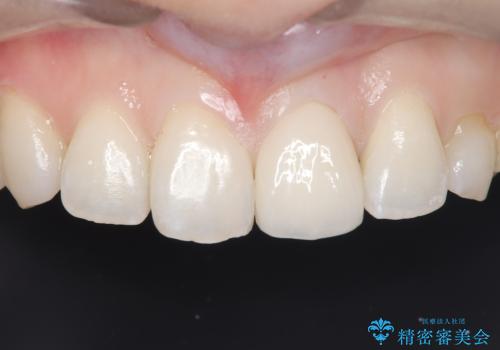

- 以前に前歯を折れた時、コンポジットレジンで修復したが、変色してきたことを主訴に来院されました。

今回は、セラミッククラウンによる修復を希望され、治療を行っています。

コンポジットレジンは、経年変化しやすい材料ですが、セラミックは変色しずらい材料となります。